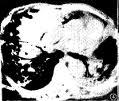

PCP肺炎PCP好發於免疫缺陷的兒童和成年人,偶發生於健康人。本病的主要臨床特點為大多數病人有發熱、呼吸困難和紫紺及乾咳等,僅根據臨床表現不易診斷。PCP胸片的典型改變為雙側瀰漫性肺泡和間質浸潤,開始由肺門向外擴展,隨之迅速實變為蝶狀陰影,肺尖和肺底很少累及。分析13例PCP的X線特點,歸納為4種形態:(1)間質肺泡浸潤;(2)輕度瀰漫性肺泡滲出;(3)中度融合性肺實變;(4)重度瀰漫性肺實變。

其他輔助檢查:X 線表現是非特異性的,10%~25%患者胸部X 線可正常。典型的X 線表現為瀰漫性肺間質浸潤,以網狀結節影為主,由肺門向外擴展。病情進展,迅速發展為肺泡實變,病變廣泛而呈向心性分布,與肺水腫相似。在實變病灶中雜有肺氣腫和小段不張,以肺的外圍最明顯。罕有氣胸或胸腔積液等胸膜病變。亦有以局限性結節陰影,單側浸潤為表現。肺功能檢查肺活量減低,肺彌散功能(DLCO)低於70%估計值。

PCP肺炎肺部X線檢查:

可見雙肺從肺門開始的瀰漫性網狀結節樣間質浸潤,有時呈毛玻璃狀陰影,一般不累及肺尖、肺底和肺外帶;有時可見肺部局限性結節陰影、大葉實變、空洞、肺門淋巴結腫大、胸水等,但多數患者合併細菌或真菌感染,X線檢查多不典型。